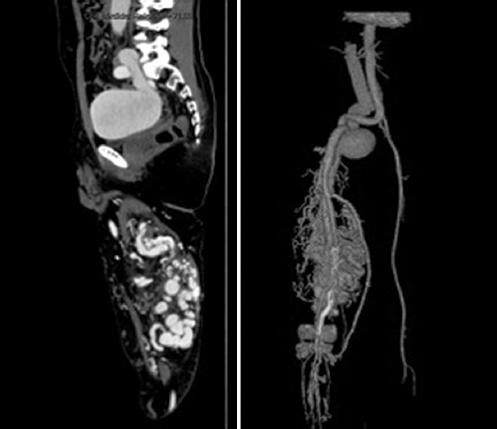

Diagnostic approach was initially performed with a transthoracic echocardiogram with a left ventricle ejection fraction of 75%, dilated right ventricle and biauricular dilation. Doppler ultrasound (US), with a vascular malformation, formed by arterial and venous turbulent flow. The angio-CT (CTA) showed dilation of the aorta and a right iliac vein aneurysm with a maximum diameter of 7.6 cm, multiple tortuous vessels through the leg, femoral superficial artery with surgical changes due to the bypass and a stent in the superficial femoral and profunda femoral arteries (Fig. 1). Six endovascular interventions were performed within 4 months, combining different embolization methods for afferent vessels occlusion. All the sessions took place in the angio-suite under general anesthesia.

Figure 1 Angio-computed tomography sagittal and 3D-reconstruction showed an aneurysm in the right iliac artery and an arteriovenous malformation on the leg with 18 multiple tortuous vessels, femoral superficial artery with surgical changes due to the bypass and a stent in the superficial femoral and profunda femoral arteries.